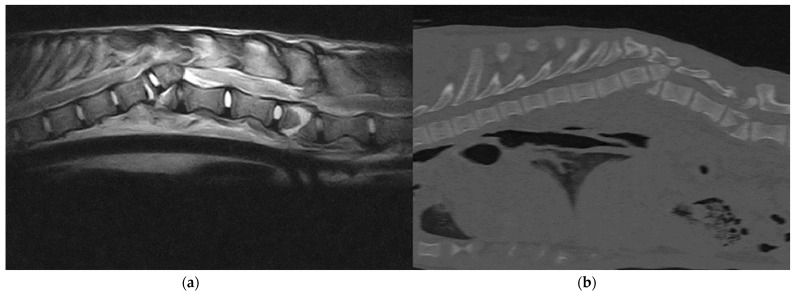

回顾了2017年至2022年在圣米歇尔Ospedale兽医医院治疗的14只C1至L7椎体骨折或脱位(SFL)的意大利狼(Canis lupus italicus)的医疗记录。导致SFL最常见的原因是“道路交通事故”。使用改良的Frankel量表将神经症状从0到6分级。C1-C5骨折1例,T3-L3骨折11例,L4-L7骨折2例。6只狼在没有治疗的情况下被安乐死,因为它们表现出没有深度疼痛感知(DPP)的截瘫。两只有运动功能的动物被保守治疗,后来其中一只因为神经损伤而被安乐死。六只狼接受了手术治疗。7只狼的神经系统恢复良好,其中6只被放归野外。我们的研究结果表明,术前患有DPP的狼可能有良好的功能恢复。

The medical records of 14 Italian wolves (Canis lupus italicus) with a vertebral fracture or luxation (SFL) between C1 and L7 treated at Ospedale Veterinario San Michele from 2017 and 2022 were reviewed. The most common cause of SFL was "road traffic accident". Neurological signs were graded from 0 to 6 using a modified Frankel scale. Spinal fractures occurred in C1-C5 in 1 case, in T3-L3 in 11 cases and in L4-L7 in 2 cases. Six wolves were euthanized without treatment because they presented paraplegia without deep pain perception (DPP). Two animals with motor function were treated conservatively, and later on one of them was euthanized because of neurological impairment. Six wolves were surgically treated. Seven wolves had good neurological recovery, and six of them were released into the wild. Our results suggest that wolves with DPP before surgery may have a good functional recovery.